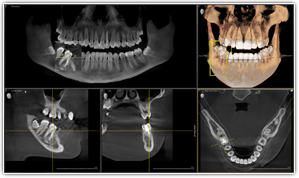

今までのCTに比べ画像が驚くほど鮮明、3D-画像がより立体的、神経の位置を詳細に把握することができ、より正しい診断が可能となりました。

歯の根元の状態や、病気、べニアの接合状態、冠修復物のセット等 術前、術後の状態把握にもその力を発揮します。

歯科治療の高度化に伴い3次元画像診断が当たり前の時代になっています。3次元画像診断では、歯、顎、口腔領域などの形態や位置関係を知ることができることから、治療及び手術を安全、確実にしかも短時間で行うことができます。

3次元画像診断は次のように歯科でのあらゆる病態の把握に非常に有効です。

歯科用CTでは、コンビーム式のスキャンを行うことで、短時間のX線照射による、歪みの少ない繊細な画像を断面で観察することができます。